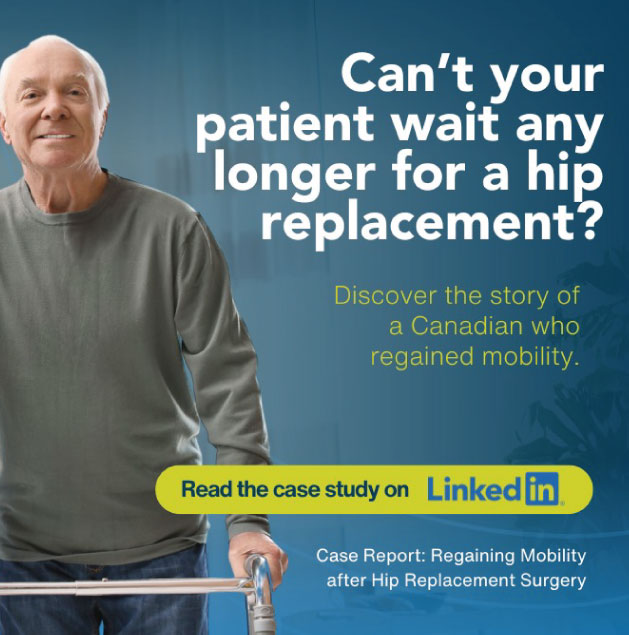

Leading the treatment of complex trauma through a multidisciplinary approach in Los Cabos.

This is your moment to return to an active life.